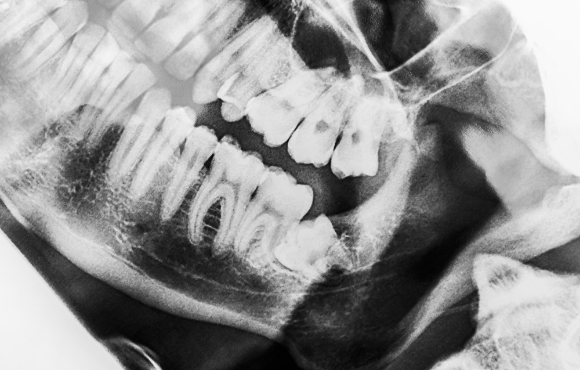

親知らずの治療

親知らずは生え方によって、歯磨きをきちんとすることが不可能な場合が多くあります。

将来的に虫歯や歯周病になってしまう可能性が非常に高く、手前の健康な歯を巻き添えにしてしまう恐れがあるため、早めに当院での診療をおすすめいたします。